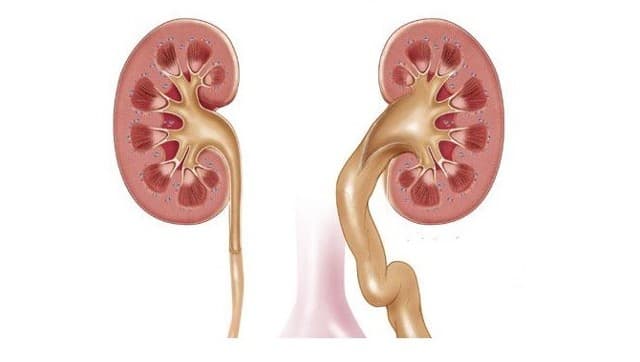

Интраренальная лоханка: рентгеновские снимки и примеры

Раздел: Фотоэссе